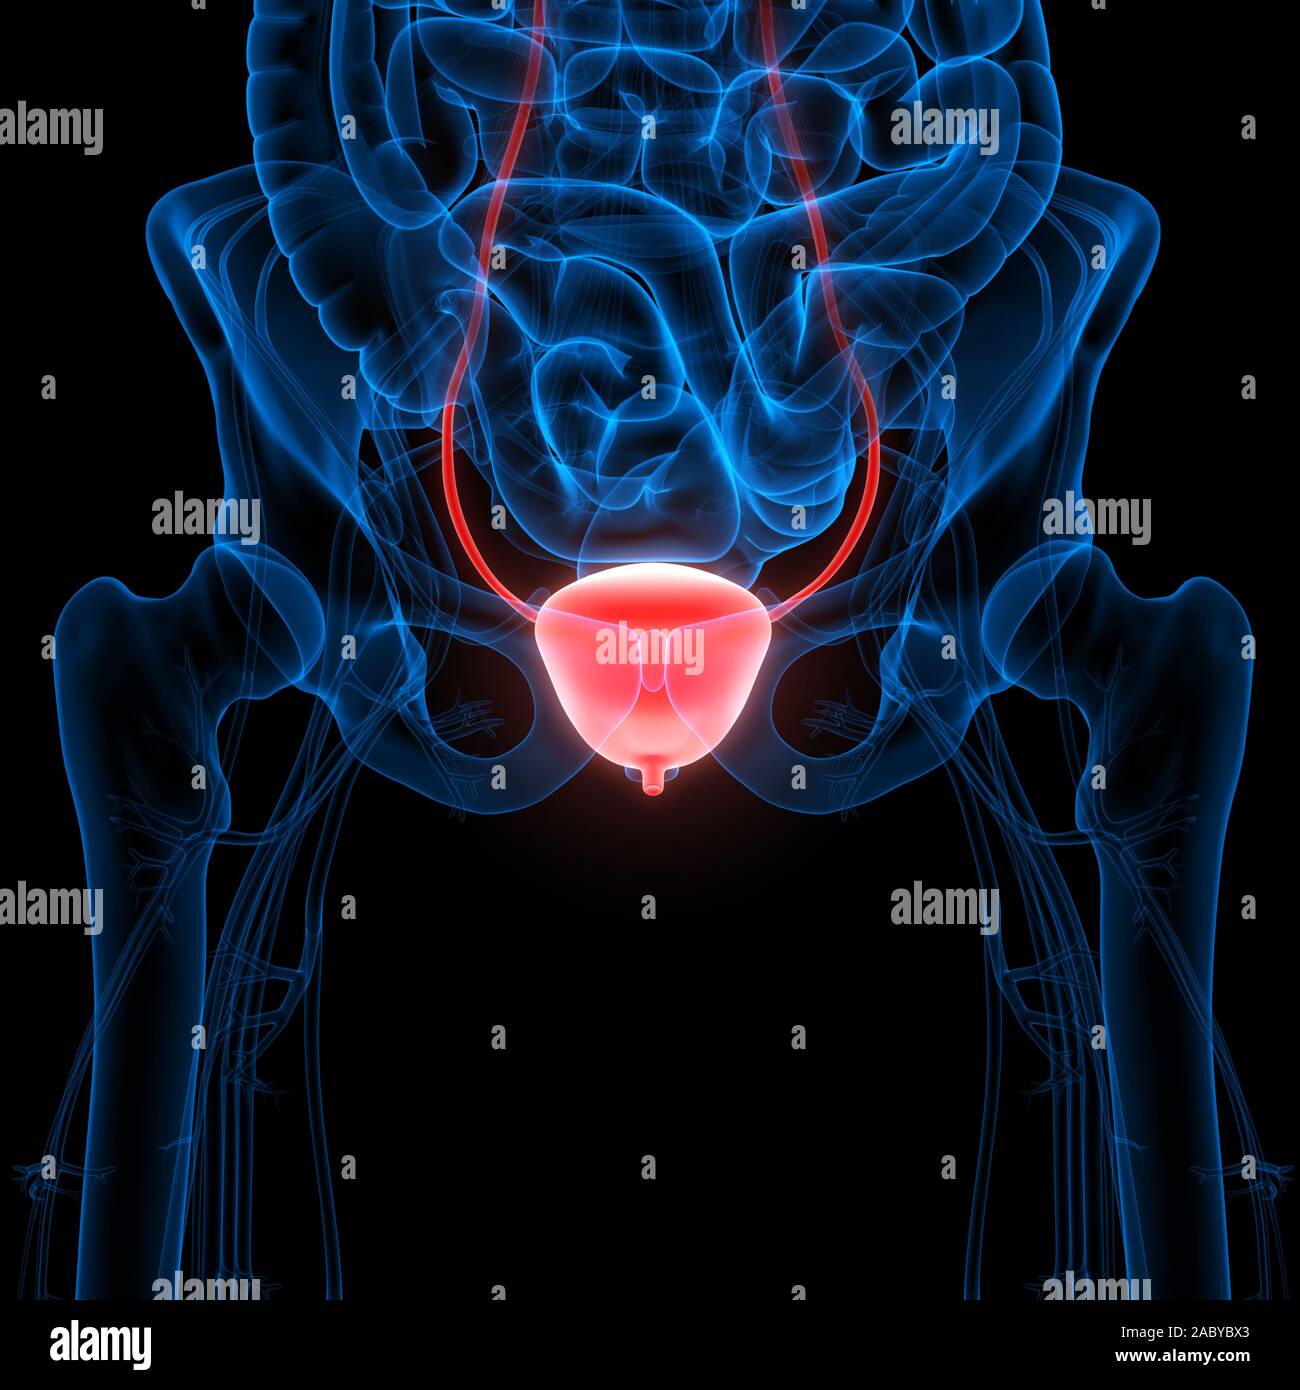

location of the bladder in the human body

Posts: location of the bladder in the human body